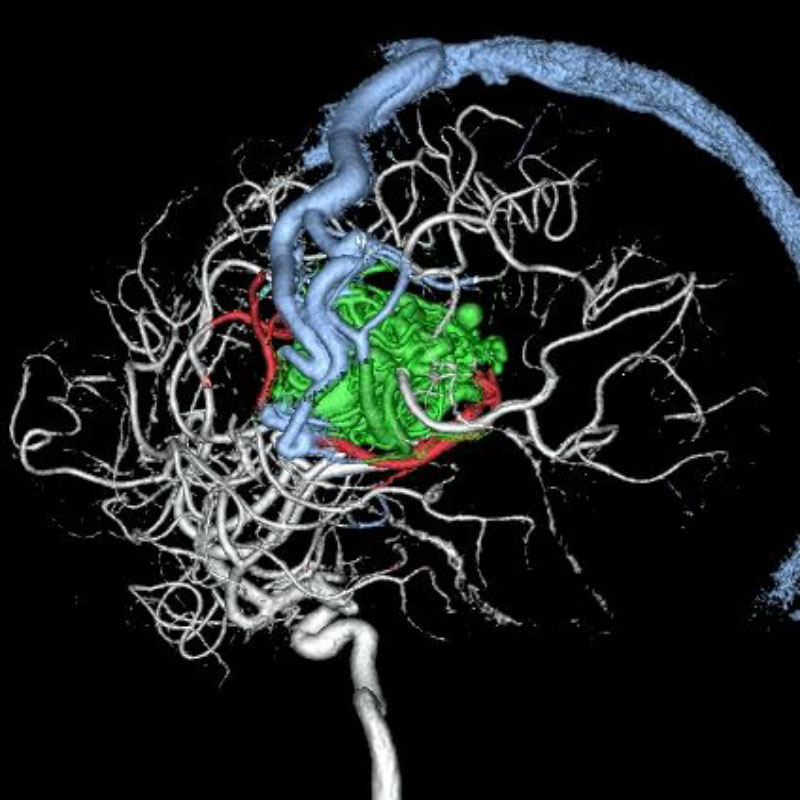

脳血管内手術症例

画像

脳動静脈奇形

血管塞栓術

松田/濵田/元永